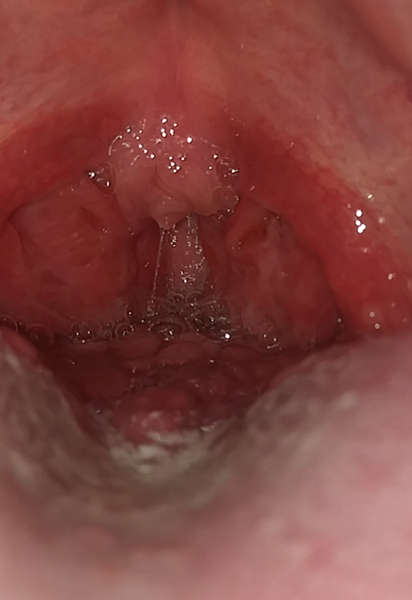

¿Tengo VPH? Bolitas atrás de la lengua

Hace varios meses me salio candidiasis oral, también tengo dolor de garganta y de estomago. También note que tengo unas bolitas en la parte de atrás de la lengua y que mi garganta esta enrojecida. El doctor que me atendió me dio medicamento pero no se me quito. Le comente todo eso al doctor y le pregunte que si era VPH y me dijo que no. Pero yo creo que si. Me gustaría una segunda opinión.